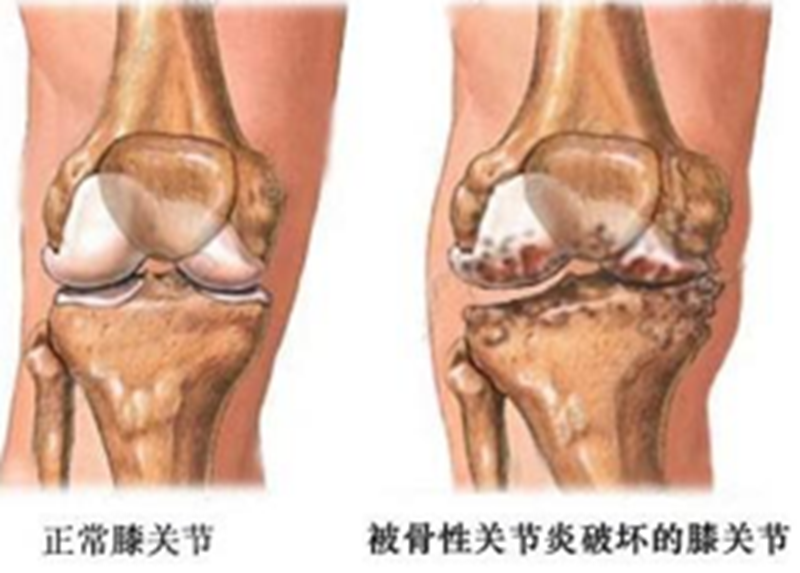

一文详解保膝治疗之胫骨高位截骨术

膝关节骨关节炎X片分级

0级:正常;

I级:关节间隙可疑变窄,可能有骨赘;

II级:有明显的骨赘,关节间隙轻度变窄;

III级:中等量骨赘,关节间隙变窄较明确,软骨下骨骨质轻度硬化改变,范围较小;

IV级:大量骨赘形成,可波及软骨面,关节间隙明显变窄,硬化改变极为明显,关节肥大及明显畸形。